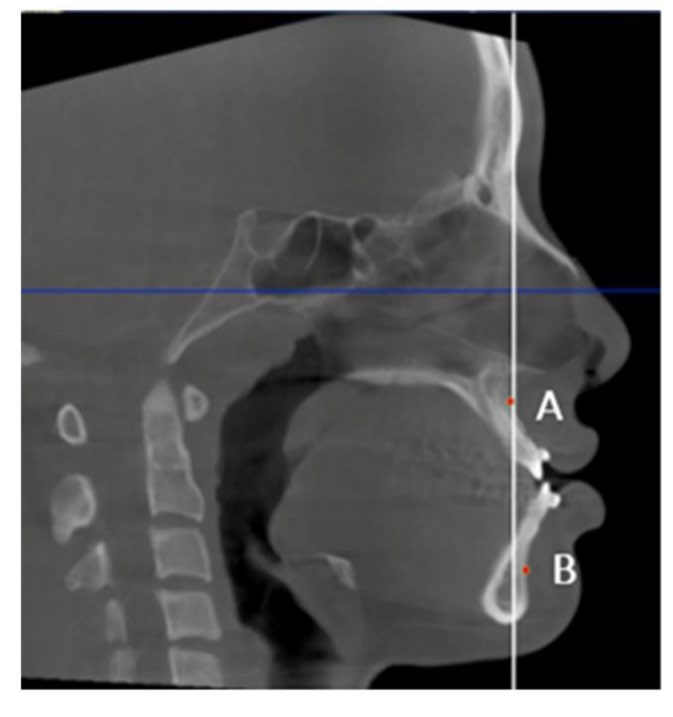

Midsagittal CBCT images were selected. Maxillary and mandibular movement was measured in mm using the difference in the distance from points A (Maxillary movement) and point B (Mandibular movement) to the Na‒PP plane at each time point (Figure 2). For airway analysis, the pharyngeal airway was divided into 3 levels according to Park’s protocol (Park et al., 2012), the nasopharynx (NP; between the PNS-V plane and CV1 plane), oropharynx (OP; between the CV1 and CV2 planes), and hypopharynx (HP; between the CV2 and CV4 planes) (Figure 3). The airway volume at each level was analyzed using the Sinus/Airway tool in Dolphin software. The area of interest was manually outlined at each airway level (NP, OP and HP) as previously described. Then, the threshold value was selected to fill the degree of airway at a detection sensitivity of 70% and the airway volume was automatically calculated in mm3. The excess selected area was manually selected from the axial and coronal CBCT images at the corresponding level (Figure 4). Airway measurements were made at T0, T1 and T2. A generalized linear model with repeated measures analysis was used to identify significant differences in airway volume among the three time points, with a P value less than 0.05 considered to indicate statistical significance. To eliminate confounding factors of the baseline volume, the altered airway volume was calculated as a percentage change before prediction analysis (Brunetto et al., 2014). The skeletal relapse was defined as the anteroposterior change in the position of the A-point or B-point from the immediate postoperative (T1) to the 6-month postoperative (T2) time point.

Figure 2. Skeletal movement measured using the distance from points A and B to the Na–PP plane (white line).